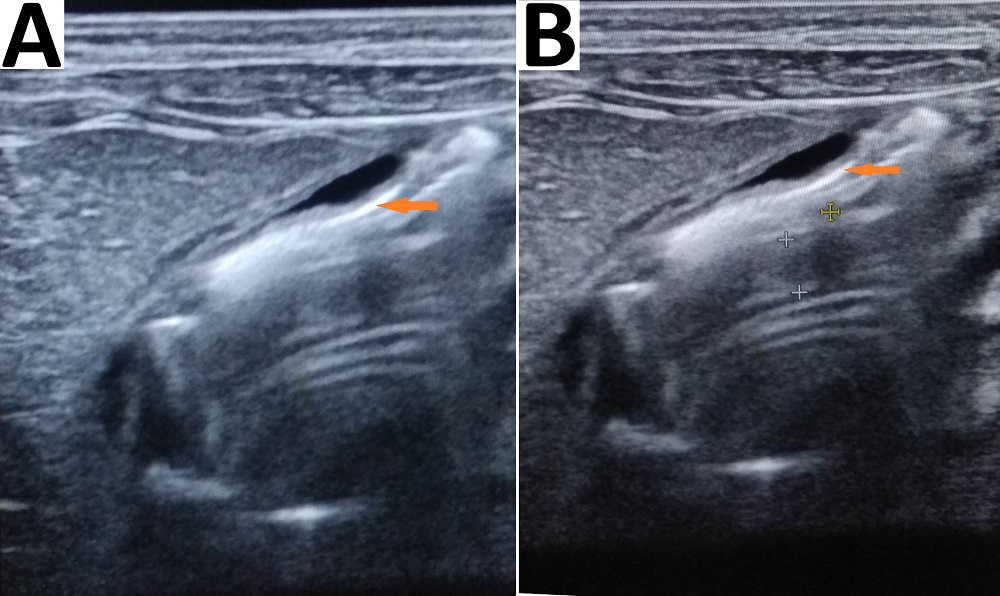

Figure 4

Photographs showing abdominal ultrasound scans performed after pyloromyotomy (Group A) with intraperitoneal blood collection (red arrow) around the pylorus (red arrow; A) and collection in Morrison’s pouch (B).

Figure 5

Photographs showing abdominal ultrasound scans performed after pyloromyotomy (Group B) with oxidized regenerated cellulose gauze patch represented by hyperechogenic line (red arrow); minimal fluid (+) around the pyloromyotomy site is also present (B).

One patient in our study who developed ileal perforation, presented after discharge with features of peritonitis (5 days postoperatively); the diagnosis was established intra-operatively during the second surgery. The cause of ileal perforation was not known, but likely due to iatrogenic injury. The trace of pyloromyotomy was represented by a faint furrow with a light yellow white, slightly edematous serosa (Fig. 3). One patient in group A with intraperitoneal blood collection (above mentioned) required blood transfusion for anemia caused by pyloromyotomy-site bleeding. The diagnosis was established by ultrasound abdomen (Fig. 4). In cases with postoperative vomiting, ultrasounds were performed to diagnose complications or those related to the placement of Surgicel®, which were normal (Fig. 5).